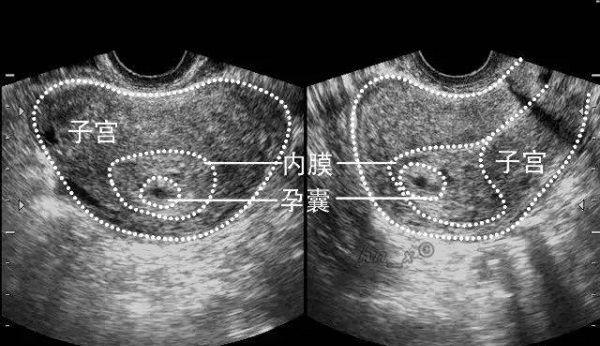

怀孕后孕囊没有胎心、胎芽

正常情况下,女性通过试管婴儿技术怀孕后6-8周的时候,就可以通过B超看到孕囊有胎心、胎芽的出现。如果在孕囊中没有发现胚胎组织的话,就代表是空囊。

试管出现空囊也就是说女性在怀孕后,由于胚胎的质量不佳,导致孕囊中没有胎心胎芽的生长发育。女性在怀孕期间身体会出现不同程度的变化。当女性怀孕初期出现空囊也会出现比较明显的症状和表现。

孕囊是怀孕最初的形态,此时胎儿还没有完全形成,但是胎芽和胎心已经出现。在试管婴儿中发生空囊的几率是相当小的,但是也不能完全避免,因此在怀孕期间女性一定要提高警惕,不要掉以轻心。